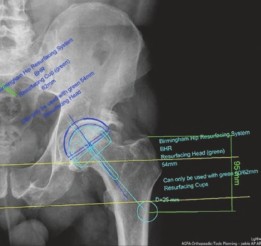

قبل الجراحة، يتم إجراء تخطيط دقيق باستخدام برامج متخصصة مثل TraumaCad. يساعد هذا التخطيط الأستاذ الدكتور محمد هطيف على تحديد حجم الغرسات المناسب (مثل كوب بحجم 62 مم ورأس بحجم 54 مم في حالة المريض) والتأكد من وضعها الصحيح لتجنب المضاعفات.

توضح هذه الصورة التخطيط الجراحي الدقيق لمفصل الورك الأيسر باستخدام برنامج TraumaCad، مع تحديد حجم المكونات وتجنب الوضعية التقوسية (varus positioning).